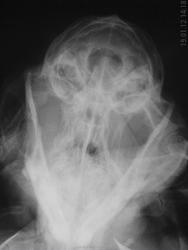

Коллега принесла на снимок любимого кота, где-то 12-13 лет от роду. Месяц назад началось слезотечение из правого глаза, лечили конъюктивит. Сейчас – правое глазное яблоко смещено кнаружи-кверху, явного экзофтальма (т.е. смещения кпереди) нет. Клиники острого процесса нет.

Извиняюсь за качество снимков, котик брыкался. В кошачей скиалогии совершенно не силен, да и с онкологией сталкиваюсь не часто. Смущает какая-то трабекулярная структура в проекции полости носа (по боковой рентгенограмме).

Нет ли проблем с носом?